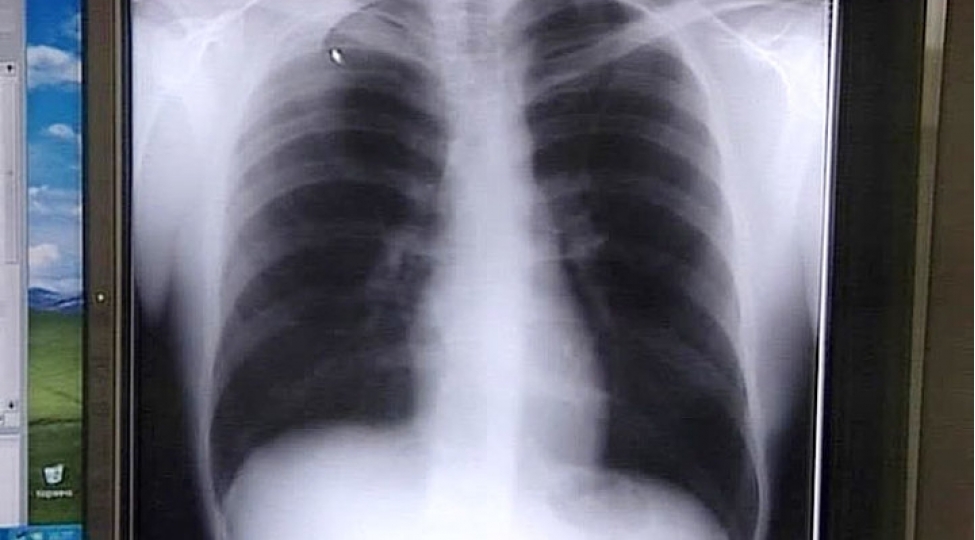

Ağciyər xərçənginin gözlə görünən əlaməti

Ağciyər xərçənginin gözlə görünən əlamətlərindən biri göz qapaqlarının sallanması ola bilər.